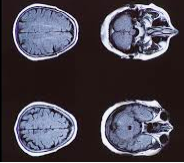

导读:MRI 引导的激光消融是一种欧美国家先进和有效的微创治疗癫痫策略。 手术仅需在头皮上做一个小切口,在颅骨上开一个小孔,与开颅手术相比,手术创伤小。对局灶性难治性癫痫(譬如HH导致的癫痫)有好的效果。关键词:小儿难治性癫痫;美国治疗癫痫;激光间质热疗 MRI 引导的激光消融是一种欧美国家先进和有效的微创治疗策略,已在不少患者中产生了有希望的癫痫发作结果。譬如下丘脑